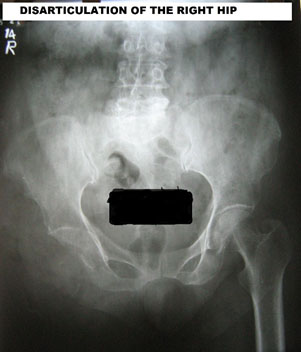

DISARTICULATION

Disarticulation is a desperate attempt to save the life when every other method to salvage the limb fails. It is a morbid and disabling surgery and is used as a procedure of desperation.

Here is an example of a 65-year-old patient who had a bipolar hip prosthesis with massive infection, not responding to repeated debridement. She ultimately responded to hip disarticulation.